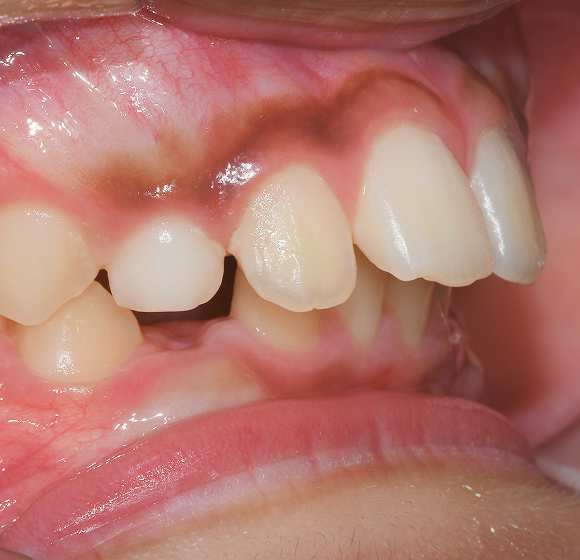

BEFORE / AFTER

전후 변화로 보는 치료사례

본 사진은 진심을담은치과교정과 치과의원에서

치료한 환자의 동일 인물 전·후 사진입니다.

개인의 구강 상태 및 관리 방법에 따라 통증 및 잇몸 염증,

턱관절 불편감 등의 부작용이 발생할 수 있습니다.

치료 전 치료 후

덧니, 삐뚤한 치열